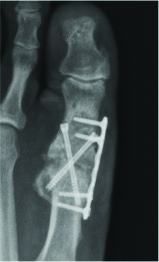

With respect to the Lapidus procedure, Barp and coworkers noted increased successful unions when using intraplate and dorsal medial plate fixation in combination with lag screw fixation in comparison to fixation with two crossed lag screws.15 These findings are consistent across the literature yet one can still achieve successful union through sound principles and two-screw fixation.

However, in the presence of osteomyelitis and deep fascial extension, authors have recommended guidelines for definitive hardware removal.33 For infection in stable osseous constructs with healed osteotomy sites and intact hardware, guidelines recommend hardware removal. One must accompany hardware removal with thorough osseous debridement of any infected bone and control of the dead space with antibiotic beads/spacers. When there is bone infection in the setting of a stable surgical site with delayed union, surgeons may choose to treat the pathogen and keep hardware intact. Unstable osseous constructs with hardware require staged reconstruction procedures with hardware removal and definitive fixation at a later interval.